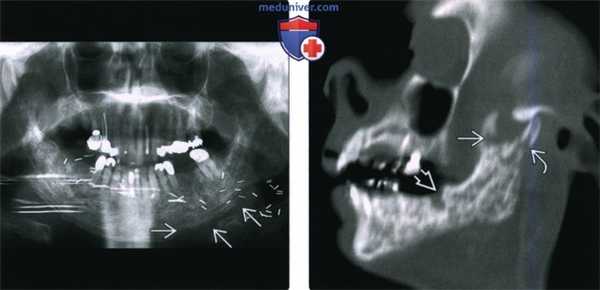

(Слева) На ортопантограмме у пациента, которому было выполнено оперативное вмешательство в сочетании с облучением полости рта, определяется диффузное утолщение и склероз нижней челюсти, утолщение трабекул и отсутствие дифференцировки кортикальной пластинки в области нижнего края нижней челюсти слева.

(Справа) При сагиттальной (под углом) реконструкции определяется, что нижняя челюсть имеет неоднородную структуру за счет множественных очаговых просветлений; определяется нарушение целостности кортикальной пластинки, утолщение и склероз трабекул и кортикальной пластинки. Обратите внимание на глубокий дефект, оставшийся после удаления моляра. Шейка мыщелка нижней челюсти и венечный отросток фрагментированы.

(Слева) На панорамной дентальной рентгенограмме у пациента, которому ранее было выполнено оперативное вмешательство и осуществлялась лучевая терапия полости рта, определяется диффузное утолщение и остеосклероз нижней челюсти, утолщение и деформация трабекул, нарушение дифференцировки кортикальной пластинки в области нижнего края нижней челюсти слева.

(Справа) При сагиттальной КТ (по углом) определяются множественные неоднородные «просветления» в кости, нарушение целостности кортикального слоя, утолщение и склероз трабекул и кортикальной пластинки. Обратите внимание на глубокую «лунку», оставшуюся после экстракции моляра. Определяется также фрагментация венечного отростка и шейки мыщелка.